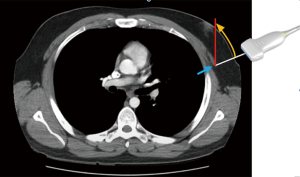

In this study, the ultrasound technique was performed as follows: a line was initially drawn connecting the nipples, extending to anterior axillary line on both sides. The linear ultrasound probe was placed along this line to identify the most distal point of lateral border of pectoralis major muscle. Once identified, the probe was adjusted so that the border aligned with the central marker (mid-probe), and this point was marked on the skin (Figure 2). This marked location corresponded to the lateral pectoral border at the nipple level, perpendicular to the chest wall (Figure 3). The distance from this point to nipple was measured using a tape measure and recorded. For the inferior border, the ultrasound probe was rotated 90 degrees and placed just below the nipple, perpendicular to the initial reference line. The same measurement protocol was followed for inferior pectoral border to nipple distance.

After double incision mastectomy, excess skin and breast tissue are removed, and chest wall is contoured flat, masculine shape. The next step is to identify the lateral and inferior borders of pectoral major muscle and mark the most lateral and inferior points on skin. It is crucial to ensure that skin markings are made perpendicular to chest wall, rather than directly anterior, as illustrated in Figure 3. This distinction explains why our study reports longer distances compared to previous studies that relied on the shadow of the pectoral muscle or the palpable border of the muscle. In those studies, the borders were not the true lateral or most inferior limits of the muscle, but rather palpable muscle bulk or shadow. Therefore, skin markings were often placed anteriorly to those points. As a result, distances from pectoral borders in these studies present shorter distances (13-15).